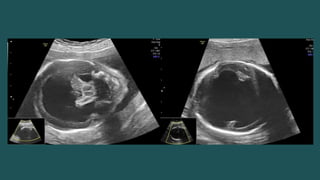

ALOBAR

 SIGNO “ SERPIENTE DEBAJO DEL

CRÁNEO”.

 SIGNO “SERPIENTE DEBAJO DEL CRÁNEO”.

• #18 Figure 13. Alobar HPE. Sagittal color Doppler US image of a fetal head shows the “snake under the skull” sign: a single anterior cerebral artery (arrow), also known as an azygous anterior cerebral artery, displaced anteriorly to run under the frontal bones, instead of between the frontal lobes as in a normally formed brain.